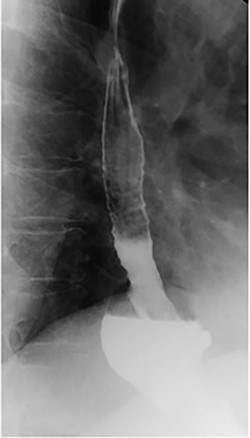

She underwent an upper gastrointestinal series that showed a normal-appearing stomach without any evidence of her prior gastroplasty, moderately sized hiatal hernia and slight delay in passage of contrast through the gastroesophageal junction (Fig. 1). On subsequent endoscopy, she was noted to have multiple loosely placed sutures within the gastric lumen along the greater curvature (Fig. 2), as well as a large-sized paraesophageal hernia.

Intraoperative endoscopy showing loose gastroplasty sutures along the greater curvature of the stomach.